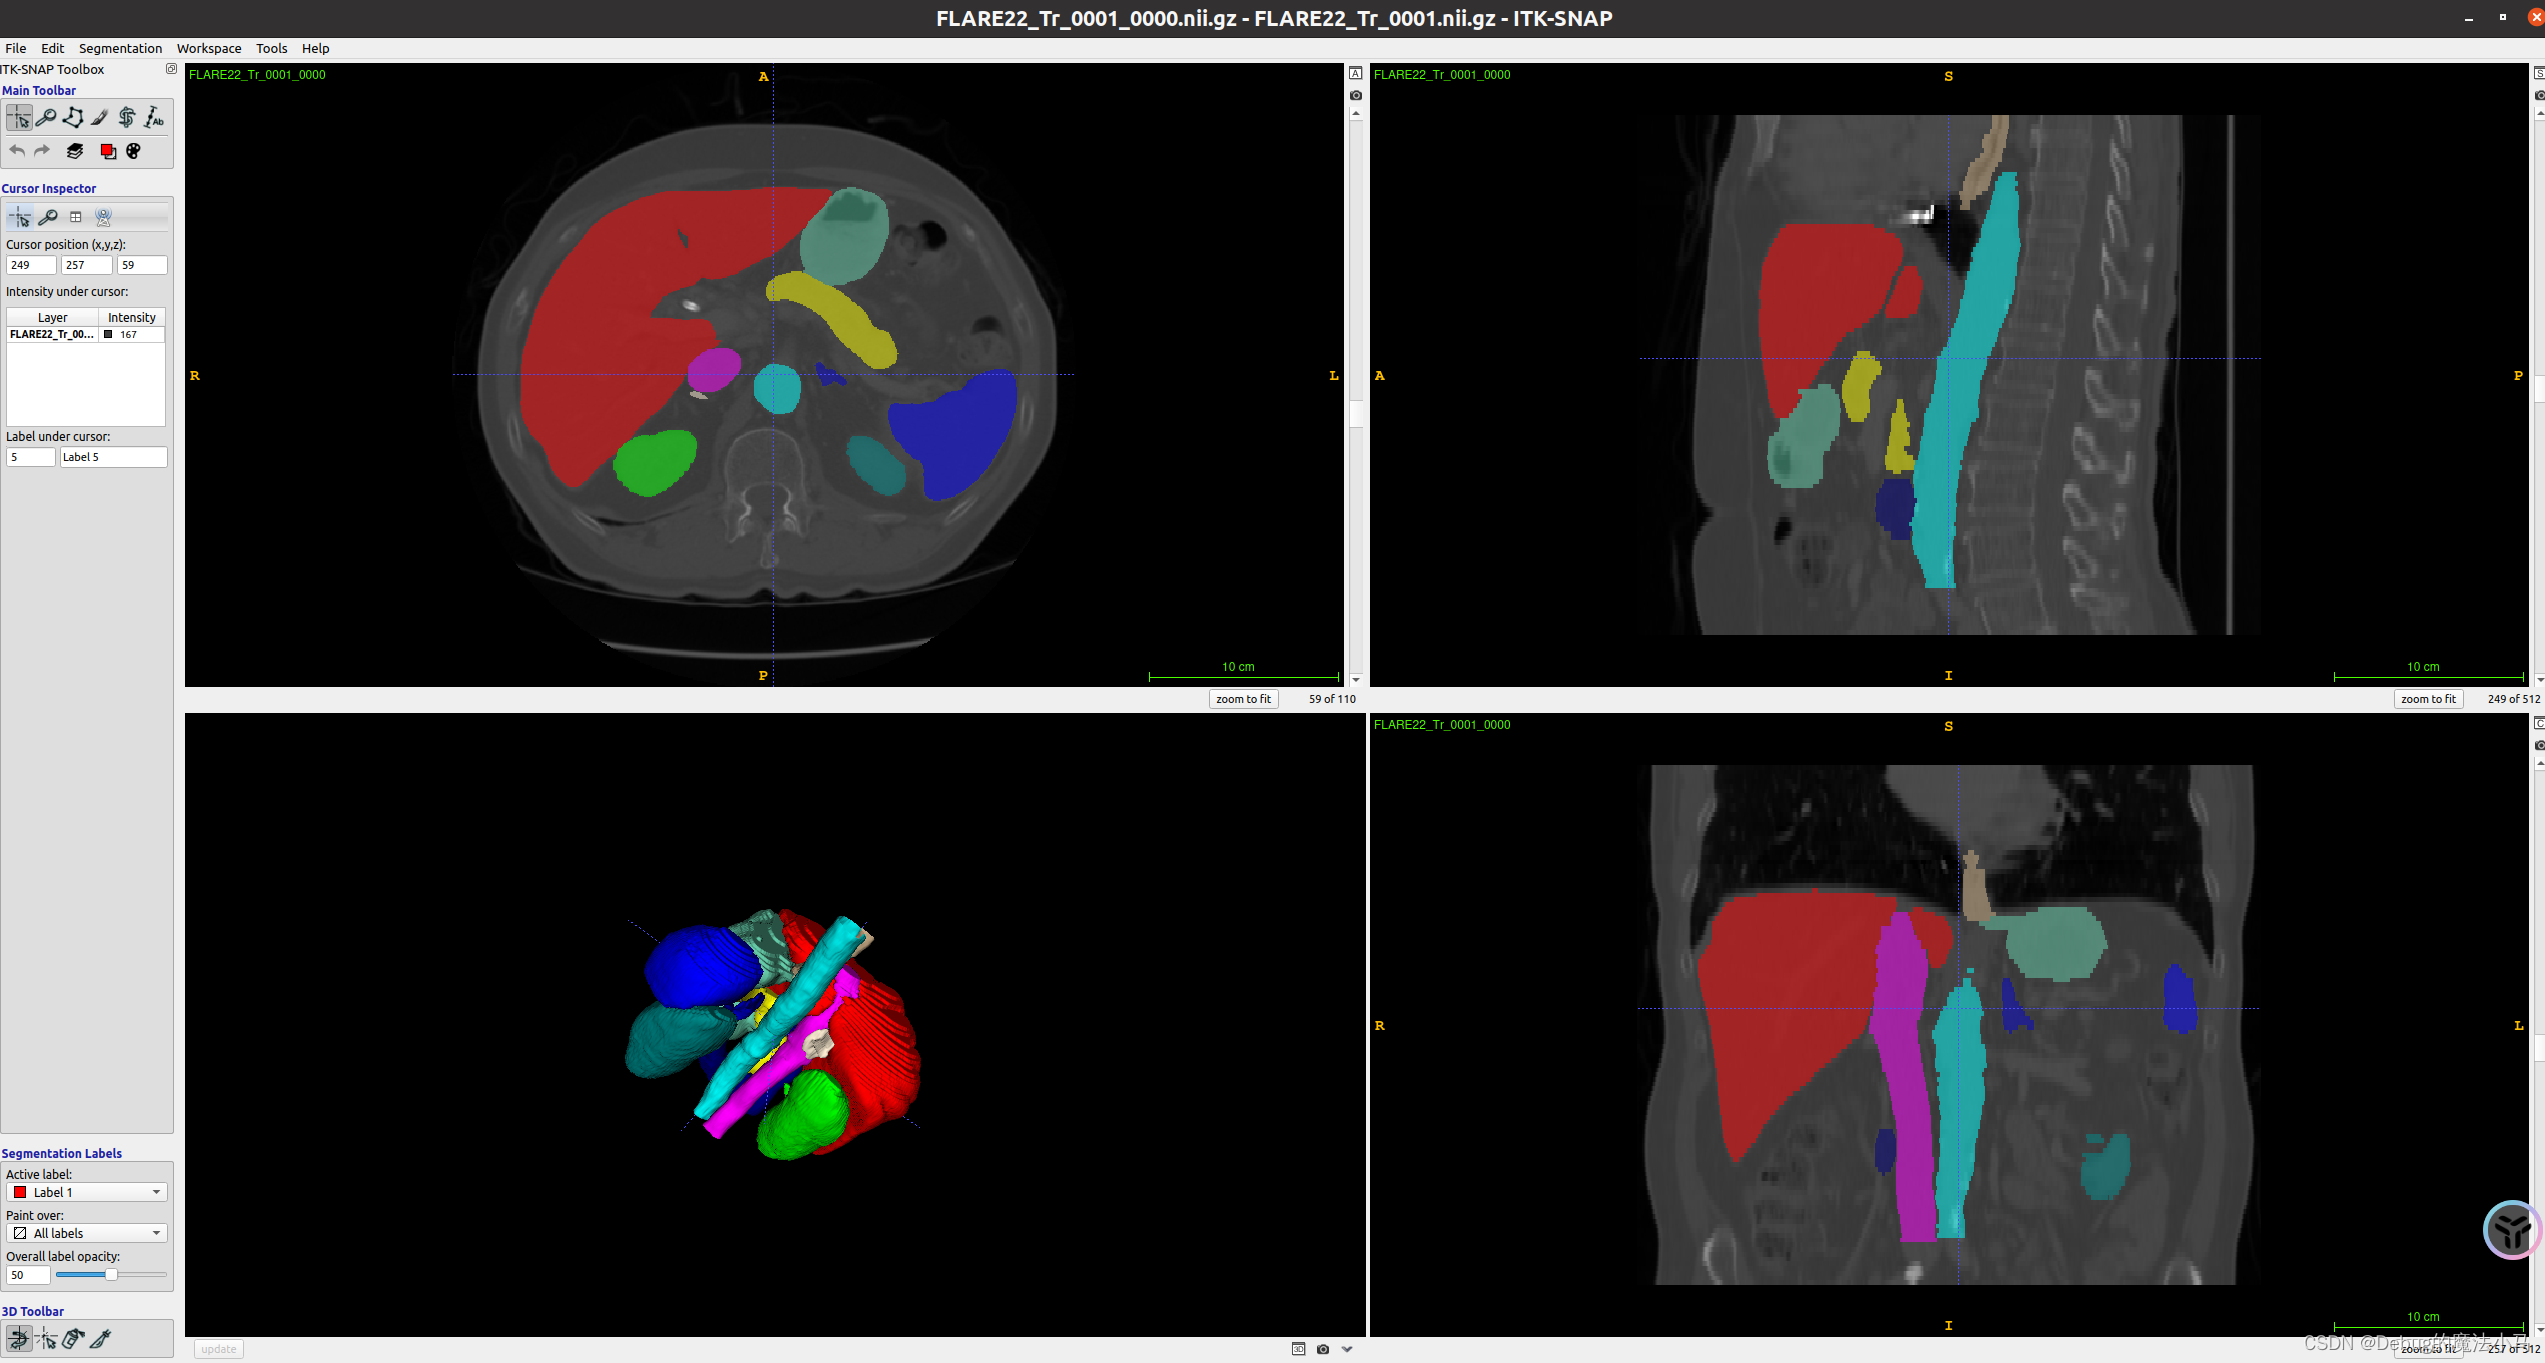

可视化

如果想可视化nii.gz文件。

先安装itksnap:

sudo apt-get install aptitude

sudo aptitude install itksnap

itksnap

再参照参考博客执行。